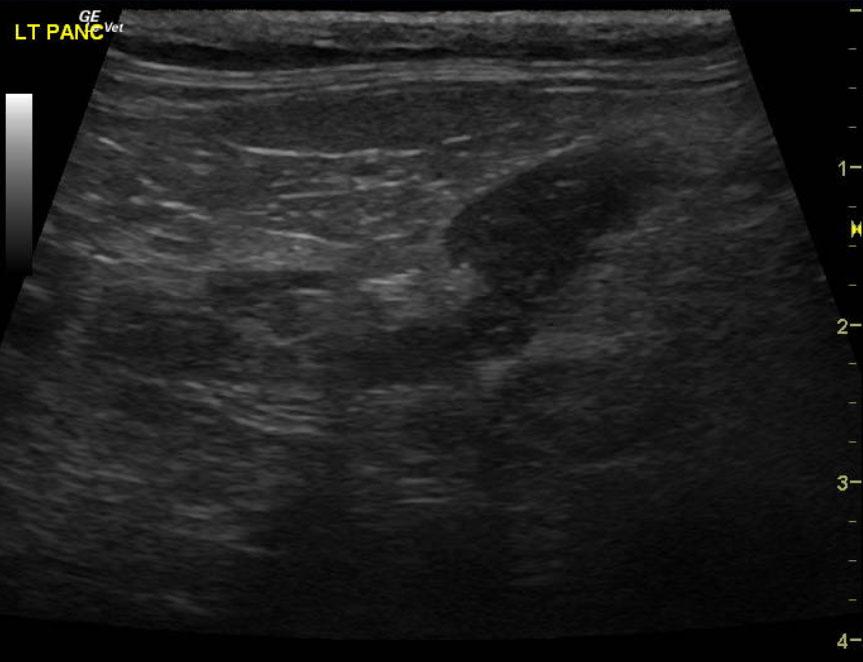

A 15-year-old MN DMH cat was presented for chronic diarrhea, hyperthyroid, dehydration, otitis externa, and periodontal disease. The CBC was markedly normal with blood chemistry revealing an elevated ALT (154,) elevated SAP (109,) hyperT4 (>10,). An IDEXX feline diarrhea panel was negative for virus, parasites, & bacteria.